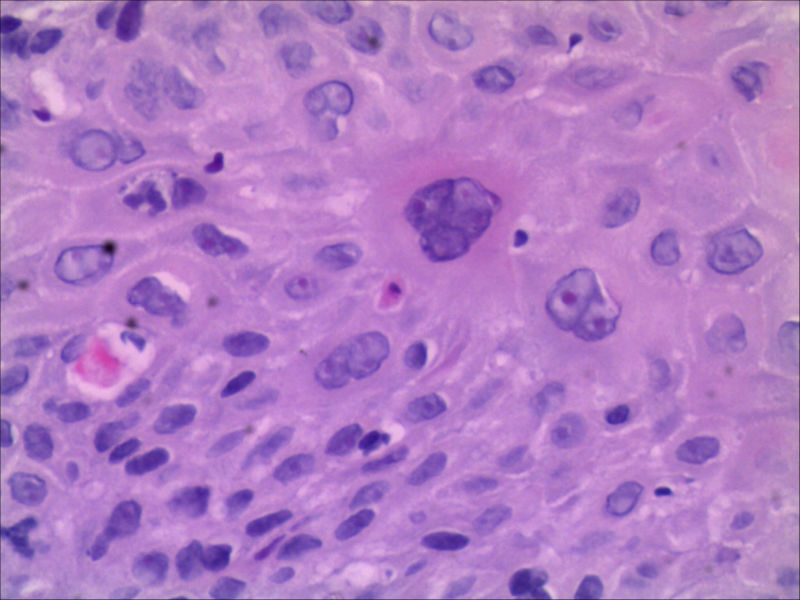

食管活检男64岁食管粗糙

图1